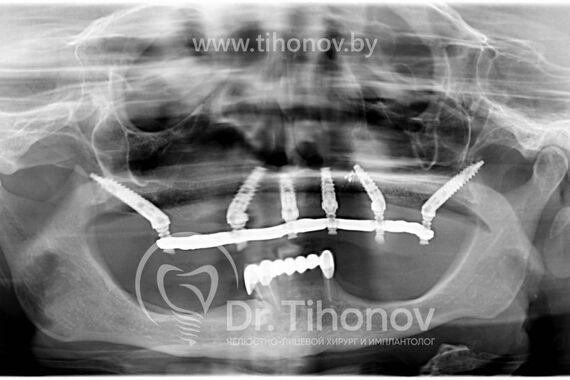

После изучения данных 3D-исследования челюстей и клинической ситуации в полости рта на очной консультации было принято решение о протезировании зубов на верхней челюсти при помощи методики All-on-6 (все на 6-ти). В день операции на верхней челюсти были удалены несостоятельные протезы и разрушенные корни зубов, установлены 6 имплантатов, в течение 4 дней был изготовлен и фиксирован несъемный металлопластмассовый эстетичный протез на верхнюю челюсть. Использование методики протезирования All-on-6 (все на 6-ти) в данном клиническом случае позволило полностью удовлетворить потребности пациентки.